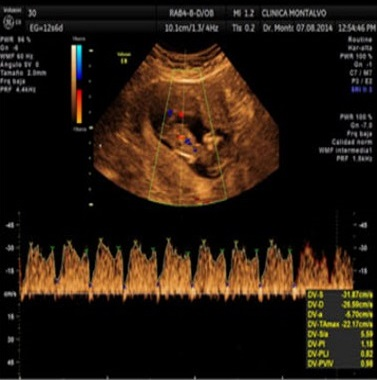

- Ecografía Doppler de la circulación fetal y

materna: Permite evaluar el flujo sanguíneo en vasos específicos, anticipando signos de peligro de

mortalidad perinatal con 2-3 semanas de antelación. Es un procedimiento indoloro e inofensivo.